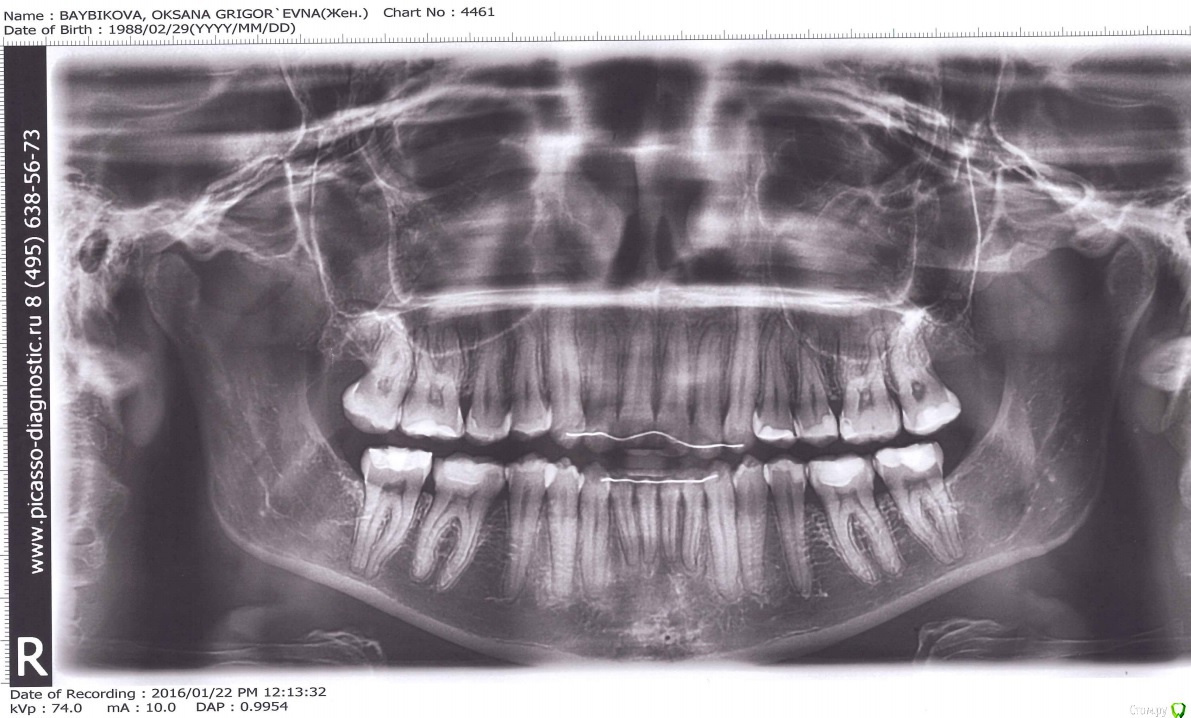

krokomot Опубликовано 12 февраля, 2016 Поделиться Опубликовано 12 февраля, 2016 Я вижу на снимке, что у вас все жевательные зубы реставрированы причем не выражены необходимые анатомические структуры бугров, вполне возможно, что проблемы с суставом из=за неправильной формы жевательной поверхности боковых зубов, если это так, то вам нужно обратьться к стоматологу-ортопеду для восстановления правильных окклюзинных взамоотношений (в случае отсутсвия проблем в оклюзии и правильном ранее проведенном ортодонтическом лечении) Ссылка на комментарий